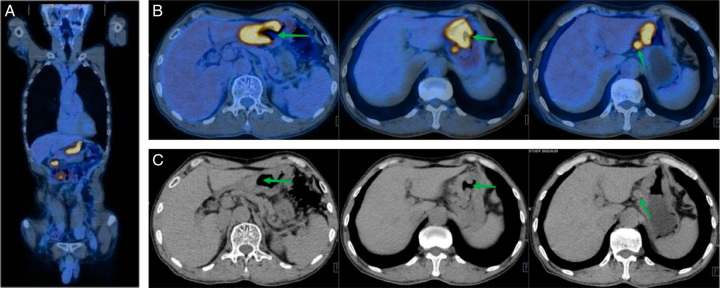

Gastric cancer is the most common type of gastrointestinal cancer in China which about 80% of patients are locally advanced or advanced when diagnosed. Surgery along brings high recurrence rate for locally advanced gastric cancer (LAGC), and neoadjuvant therapies are needed. The use of programmed cell death-1 (PD-1)/programmed death-ligand 1 inhibitor nowadays improved the disease-free survival for LAGC, however, only <35% of patients achieved pathologic complete response (pCR) after neoadjuvant therapy nowadays. Therefore, new regimens are needed to be investigated. Gastric artery chemoembolization is applied to metastasis gastric cancer and researches showed interventional therapy can enhance the antitumor effect of PD-1 inhibitor. Here, for the first time, we combined gastric artery chemoembolization with tislelizumab (a PD-1 inhibitor) for neoadjuvant therapy of a patient with LAGC. The patient achieved pCR after a D2 resection and tumor regression grade score was 1. After surgery, the patient received tislelizumab 200 mg per 3 weeks, and showed no sign of recurrence after 6 months of follow-up. The study indicated the use of tislelizumab and gastric artery chemoembolization for neoadjuvant therapy may bring a better pCR rate and prognosis of LAGC.